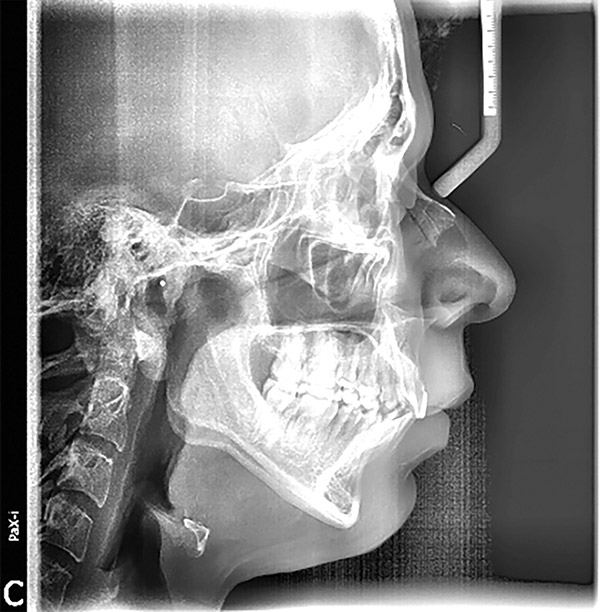

Se presenta un paciente de 25 años de edad. Radiográficamente se observa clase II esquelética, hiperdivergencia (Figura 1), en la fotografía extraoral de sonrisa el paciente se muestra con apiñamiento severo y la mordida profunda (Figura 2).

Figura 1. Radiografía lateral de cráneo.